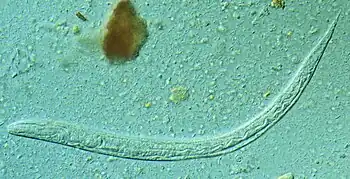

Capillaria hepatica is a parasitic nematode which causes hepatic capillariasis in numerous mammal species, including humans.[8]

-

Capillaria hepatica tissue -

C. hepatica